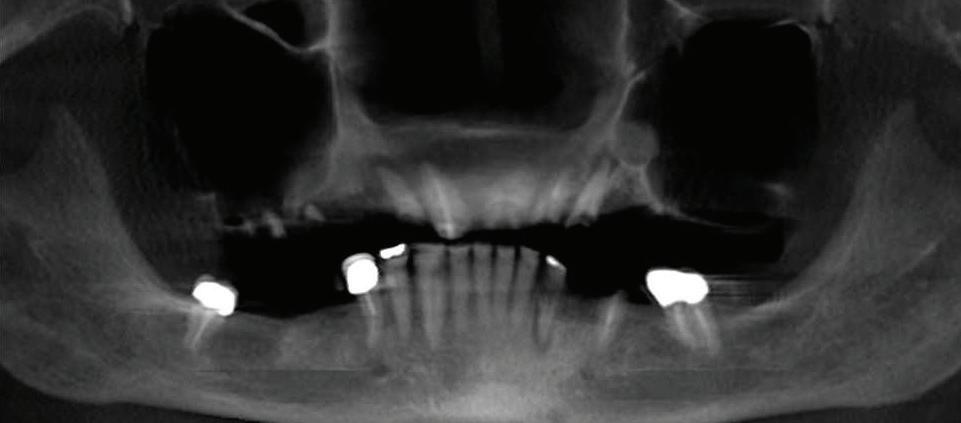

Submitted By Sivakumar Sreenivasan, DMD, MDS Dental Implant Center of Rockville

Can just four implants replace all of the teeth on the top or the bottom of your mouth? Thanks to advances in dental implant technology, that answer is a resounding yes.

Tooth loss is extremely common among adults, especially as we age. Rather than living with the discomfort and hassles of dentures, many people are opting for what is called “all-onfour” dental implant restoration.

An implant is a small titanium

screw that fits inside your jawbone and replaces the root-part of a missing tooth. Minor surgery is required to insert the implants. Once the implant is in place, a crown is attached to give you a highly realistic-looking and functional prosthetic tooth.

You do not need a dental implant for each and every one of your missing teeth. All you need is four precisely placed implants on the top of your mouth, and four on the bottom, to restore your full smile. That’s the beauty of the all-on-four. And because the implant is made of titanium, it has the unique ability to fuse to living bone and function as part of it. So eventually, the dental implant becomes part of the jawbone and serves as a strong, longlasting foundation for your new teeth.

Besides ensuring that your implants are permanently fixed in place, this bone fusion has another important benefit: it prevents future bone loss in the jaw. This helps to maintain a more youthful facial structure – and better

Please see “All-On-Four,” page 62